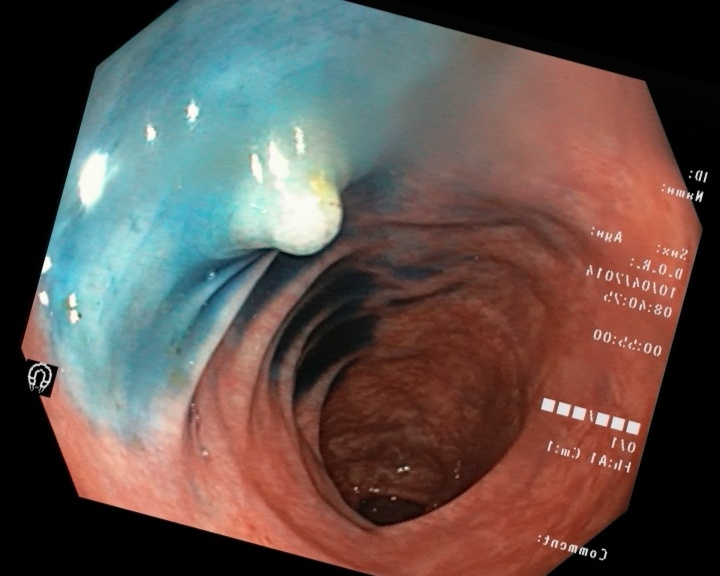

3. KvasirV2 dataset (Pogorelov et al., 2017) is a dataset containing 8000 images from inside the gastrointestinal (GI) tract. The data distribution of this dataset is balanced and can be categorised into 8 classes related to anatomical landmarks and endoscopic polyp removal, listed as ’dyed-lifted-polyps’, ’dyed-resection-margins’, ’esophagitis’, ’normal-cecum’, ’normal-pylorus’, ’normal-z-line’, ’polyps’, and ’ulc-erative-colitis’. Each class consists of 1000 sample images and all of the images have been annotated and sorted by experienced endoscopists.